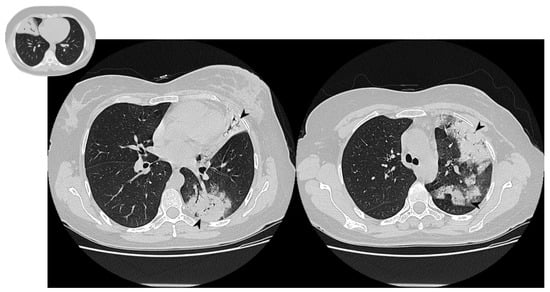

Figure 13. Presence of atoll signs (white arrowheads) in a patient with COP, which were still recognizable despite steroid therapy.

3.5. Atoll Sign

Of all four atoll signs, only one has been observed at follow-up HRCTs (Figure 13, Table 8).